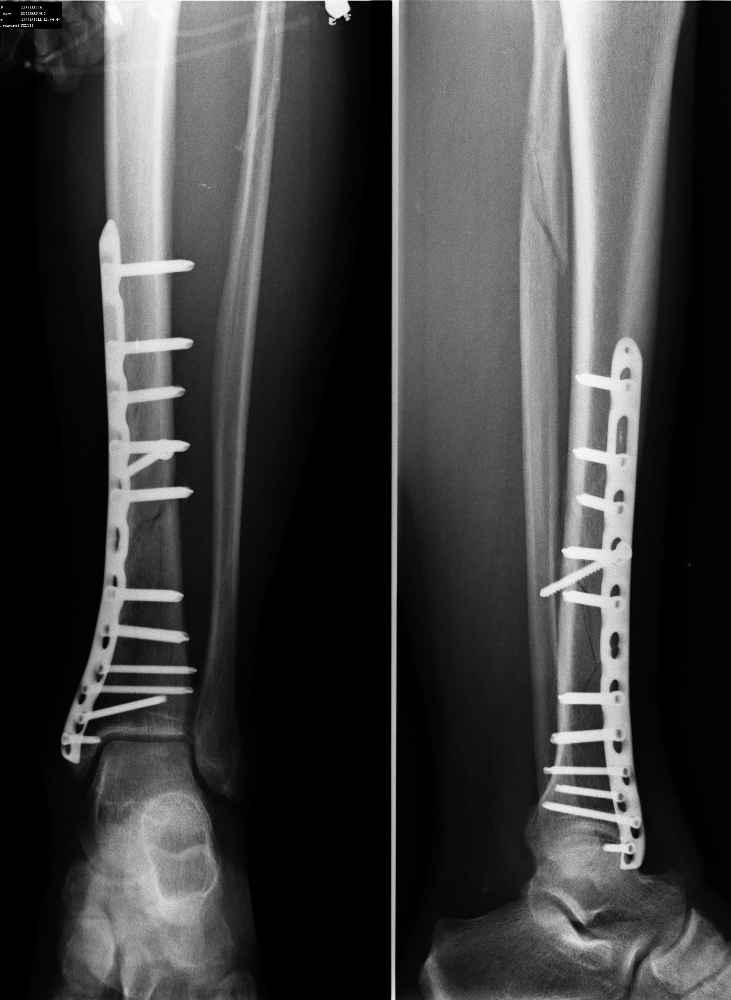

Прошу совета! Пациент 28 лет, винтообразный перелом большеберцовой кости от 19.02.2011.

(падене на коньках), остеосинтез через 4 часа, пластиной с угловой сабильностью.

Послеоперационный период протекал гладко. На р-граммах через 5 недель и 9 недель после МОС

картина без существенных изменений. Перелом малоберцовой кости также без изменений. Можно

ли говорить на данном этапе о замеленном сращении переломов?